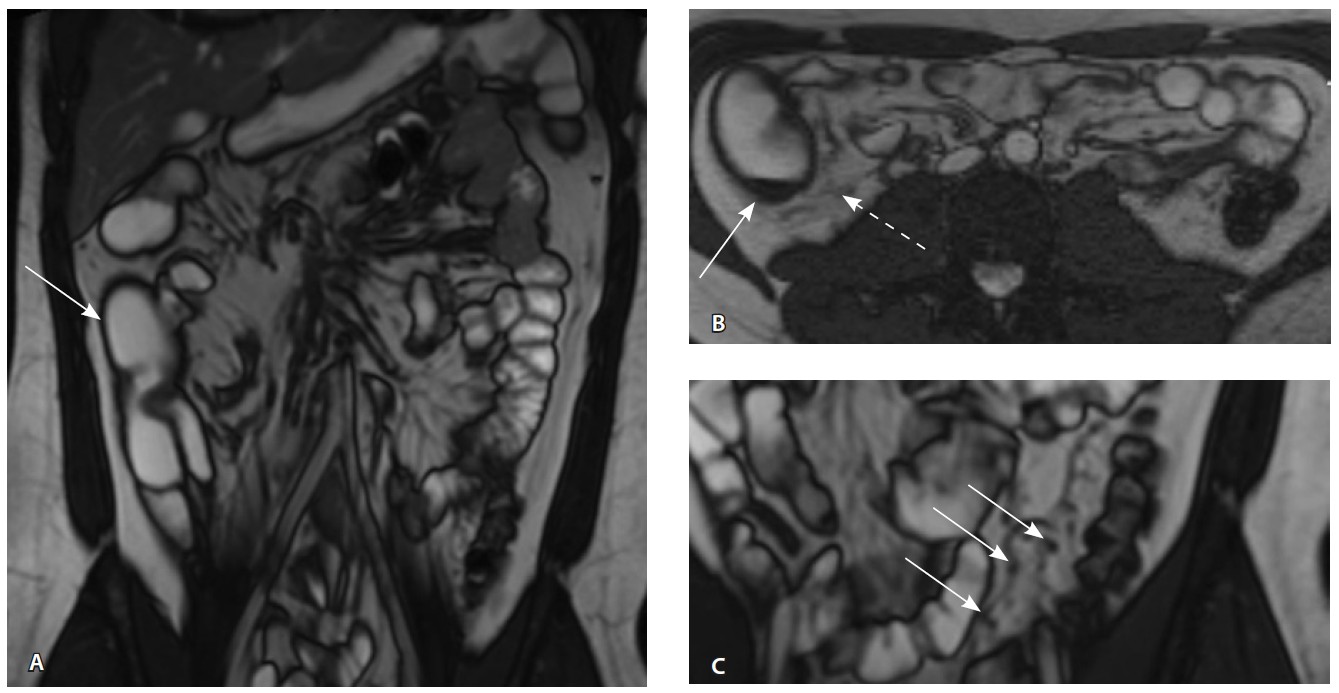

Назначена ГИБТ адалимумабом (препарат Хумира) по стандартной схеме 160 мг п/к (неделя 0), 80 мг п/к (неделя 2) с последующим плановым поддерживающим режимом 40 мг п/к каждые 2 недели. Через 9 месяцев установлена эндоскопическая ремиссия, однако сохранялась концентрация фекального кальпротектина более 2000 мкг/г. Через год жалобы возобновились, тогда же впервые была выявлена задняя анальная трещина. Выполнена магнитно-резонансная энтерография, обнаружены воспалительные изменения, характерные для БК (рис. 2 и 3).

Рис. 2. Магнитно-резонансная энтерография, Т2-взвешенное изображение: А, В – фронтальная проекция; Б – аксиальная проекция. Наблюдается отсутствие гаустрации в восходящем отделе ободочной кишки, утолщение ее стенки до 5 мм (стрелка), снижение магнитно-резонансного сигнала от прилежащих отделов клетчатки, ее неоднородность (пунктирная стрелка), увеличение лимфатических узлов до 6 см в диаметре по ходу сигмовидной кишки (стрелки)

Рис. 3. Магнитно-резонансная энтерография, Т1-взвешенное изображение после внутривенного контрастного усиления (гадобутрол, 5 мл): А – фронтальная проекция, Б – аксиальная проекция. Наблюдается выраженное усиление интенсивности сигнала от восходящего отдела ободочной кишки (стрелка), усиление сигнала от окружающей клетчатки (пунктирная стрелка)